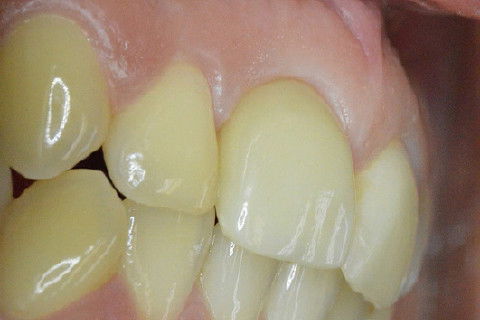

Retorno após 9 meses da instalação de coroa metalo-ceramica parafusada

Paciente com implante feito em curso de atualização, chega ao consultório para reabertura e coroa metalo-ceramica unitária, com grande depressão gengival na vestibular do elemento 11. Feita a reabertura com concomitante enxerto de tecido conjuntivo para otimizar os tecidos moles, aguardamos 3 semanas para inicio das moldagens para a coroa temporária. Após colocação e ajustes da coroa temporária parafusada, aguardamos 3 meses para completa maturação dos tecidos e então fizemos nova moldagem, com personalização do transferente para moldeira aberta individual e fizemos coros metalo-cerâmica parafusada.